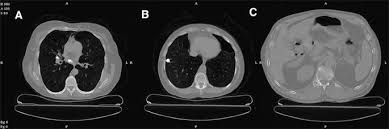

Old Granulomatous Disease Axial Ct Image Shows Multiple Small High Download Scientific Diagram